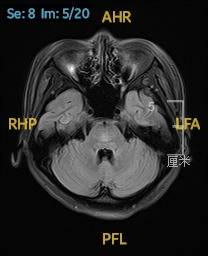

2023.02.24颅脑MR平扫示双侧基底节区及桥脑异常信号,考虑渗透性脱髓鞘综合征,见图3。

图3 2023.02.24颅脑MR成像示双侧基底节区及桥脑见对称性片样长T1长T2信号,FLAIR呈高信号。脑室、脑池、脑沟、脑裂未见明显异常。中线结构居中。